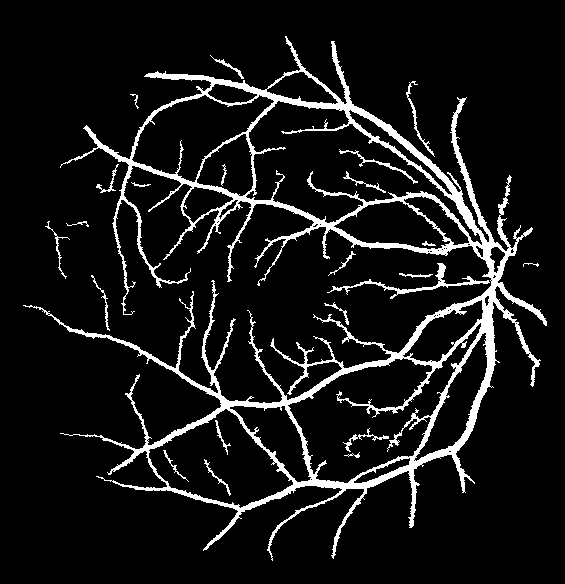

Refer to caption Refer to caption Refer to caption Refer to caption

(a)                                                                          (b)

(c)                                                                          (d)

Figure 9: Ground truth (left) and segmentation result (right): (a) and (b) are the images from DRIVE dataset, (c) and (d) are the images from the STARE dataset

V-B Vessel Segmentation Performance

The segmentation performance of the proposed model on three public available datasets is given in Table IV. It can be observed that the proposed model can achieve more than 95%percent9595\% segmentation accuracy on the DRIVE, STARE and CHASE_DB1 datasets, with the highest accuracy score Acc=96.0%𝐴𝑐𝑐percent96.0Acc=96.0\% achieved in the DRIVE dataset. Some exemplary segmentation results are shown in Fig.9. When treating the unknown regions as background regions, AUC=0.833 of trimap is 2.6%percent2.62.6\% lower than the proposed model while Acc of trimap is similar to the proposed model. In addition, Se=0.679𝑆𝑒0.679Se=0.679 of trimap is 5.7%percent5.75.7\% lower than the proposed model. These observations show that trimap can already have good segmentation performance, which indicates that the selection of region features is very effective in segmenting blood vessels. From Table IV, it can be observed that the model with vessel skeleton extraction can achieve more than 5%percent55\% increase of Sensitivity𝑆𝑒𝑛𝑠𝑖𝑡𝑖𝑣𝑖𝑡𝑦Sensitivity and 2%percent22\% increase of AUC𝐴𝑈𝐶AUC compared with the model without vessel skeleton extraction while Acc𝐴𝑐𝑐Acc of the model with vessel skeleton extraction is similar to the model without vessel skeleton extraction, which demonstrates the effectiveness of vessel skeleton extraction.